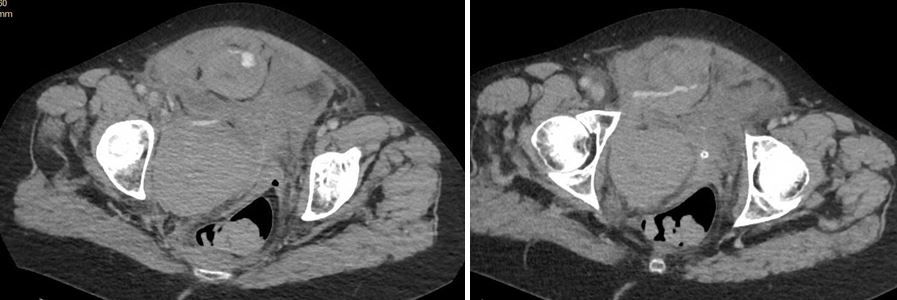

The 62-year-old woman says she nearly fainted and feels weak and nauseated. Her BP is 77/49 mm Hg and she is retaining urine. Does the CT scan offer clues to a Dx?

Vital signs and physical examination. Vital signs are normal except for blood pressure of 77/49 mm Hg and heart rate of 108 beats/min. Physical exam is notable for suprapubic swelling and tenderness. It is otherwise normal with no visible hematomas.

Imaging: See CT cuts below